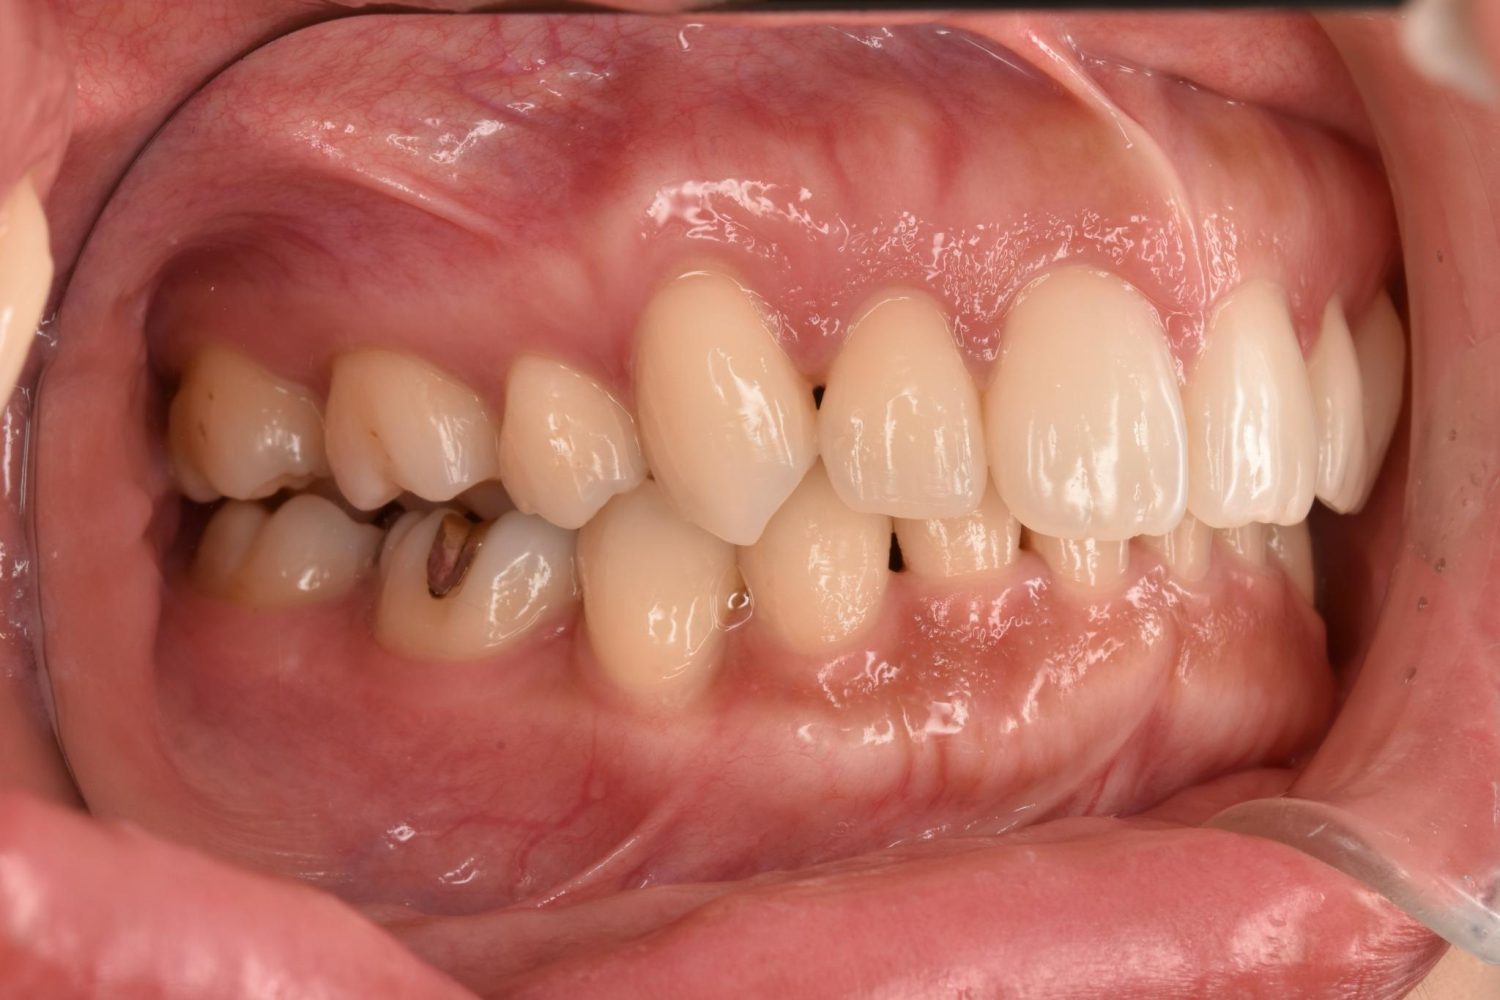

| 主訴 | 20代女性の患者さん。右上の八重歯が突出しており、前歯の見た目にコンプレックスを抱いていた。下顎の左右第2小臼歯(5番)が舌側に大きく傾斜しており、食事の際に、食べかすが詰まりやすく日常的に不快感を覚えていた。噛み合わせの改善と、見た目のバランスを整えたいという希望があり、矯正治療を行うことになった。また、目立ちにくい方法で治療を進めたいという意向から、マウスピース型装置の矯正 “インビザライン”を希望。 |

| 治療内容 | 下顎の左右第2小臼歯(5番)は舌側に大きく傾斜しており、矯正治療における歯の移動効率や全体の歯列バランスを考慮し、便宜抜歯を行った。また、上顎の左右第1小臼歯(4番)についてもスペース確保の目的で抜歯を実施し、全顎的な歯列の配列を円滑に進められるよう計画。矯正装置は、患者さんのなるべく目立ちにくい治療を行いたいという強い希望とライフスタイルに合わせて、マウスピース型矯正装置「インビザライン」(※1)を採用。抜歯が必要となる矯正治療は、診断・治療の難易度が高い方法である。当院ではCTやセファログラムなどの先進的な設備を完備し、多角的な診査診断と豊富な臨床経験をもつ理事長による治療を行うことで、このような難症例にも対応可能。 また、当院は矯正治療だけでなく、むし歯治療やクリーニングなどの一般歯科・予防治療も一貫して管理する包括的な審美治療を行う総合クリニック。治療中にむし歯などの問題が見つかっても、すぐに対応できるため、患者さんの通院の負担をできる限り抑えたスムーズな対応が可能。矯正専門医院ではできない包括的なサポート体制こそが、シャングリラデンタル横浜歯科矯正歯科で矯正治療を受けるメリットである。 矯正治療中は定期検診で経過の確認とクリーニングを行い、必要に応じて治療計画の見直しやマウスピース型装置の追加を行った。患者さんの高い装着遵守率も相まって、歯列は順調に整い、機能的にも審美的にも良好な結果をえることができた。 (※1)未承認医薬品等であるため医薬品副作用被害救済制度の対象とはならない可能性があります。 |